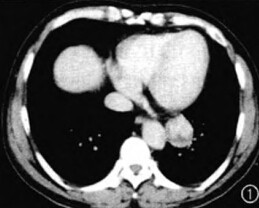

检查:胸部CT示左下肺叶内基底段类圆形肿块影,边界较光滑,密度欠均匀,其内可见点状高密度钙化影,CT值23-55Hu,大小约50.9mm x35.5mm x34.5mm,纵膈未见肿大淋巴结,气管及左右主支气管通畅。增强扫描:病灶呈不均匀明显强化,上部呈软组织密度影,下部呈囊样密度影。

诊断:左肺肿物性质待查(术前) 肺透明细胞瘤(术后) 治疗:行左肺叶切除术,术中见肿物位于左肺下叶内,大小约55mm x45mm x18mm,肿物切面囊实性,囊内容物已流出,实性区灰白灰褐色,局部坏死,内见钙化。病理诊断为肺透明细胞瘤。